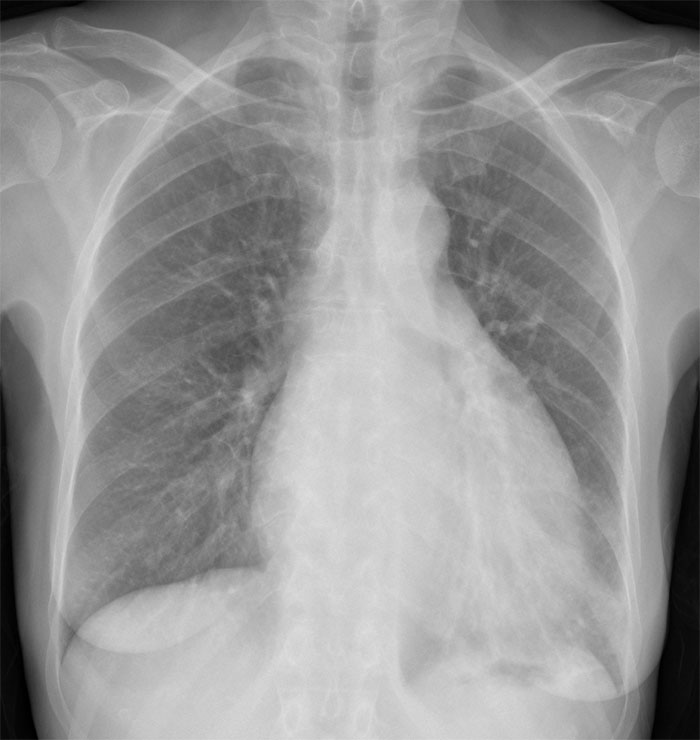

El nombre de este signo se refiere a la forma de la silueta cardiaca en la radiografía posteroanterior en bipedestación, en pacientes que tienen un importante derrame pericárdico. El agua se acumula en la parte más inferior del espacio pericárdico, mientras que la parte superior, con menos líquido, es más estrecha. La forma se ha comparado a una antigua botella de agua (tipo matraz).